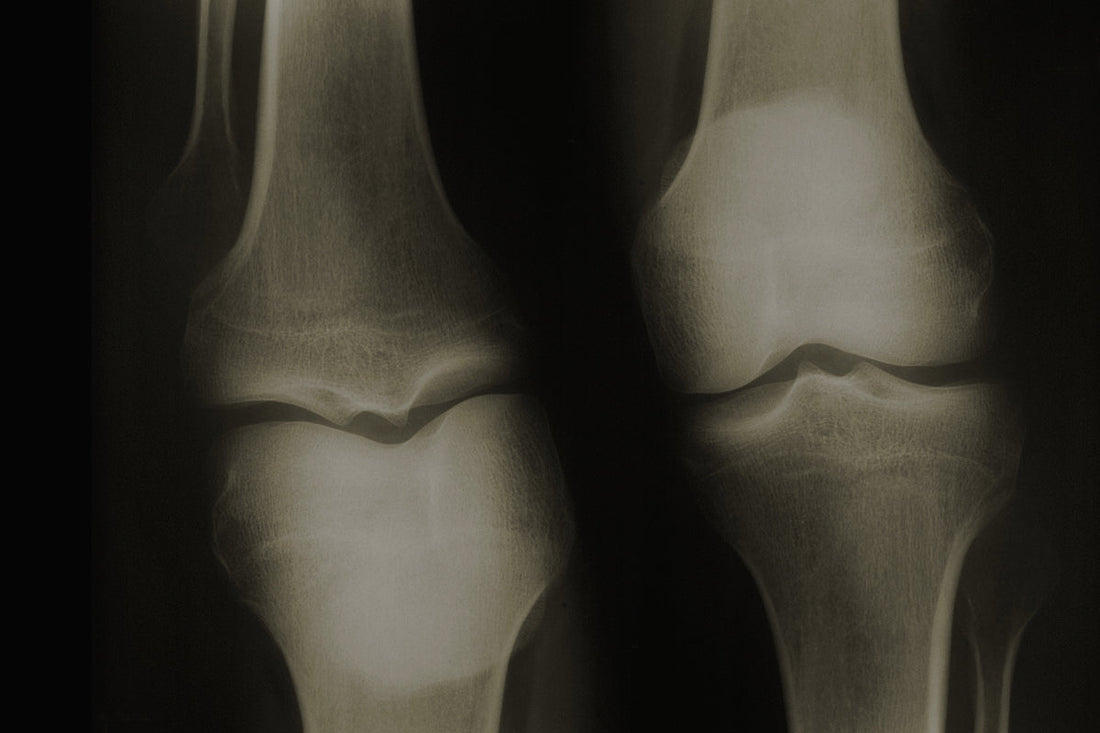

¿Cuál es el mejor antiinflamatorio para la artrosis natural?

La artrosis es una afección degenerativa que afecta al cartílago de las articulaciones, provocando dolor, rigidez, inflamación y pérdida de movilidad, por lo que incide directamente en el día a... Leer más...

Antiinflamatorio natural para los huesos: una solución eficaz y segura para el dolor articular

El dolor en las articulaciones es una molestia muy habitual, no solo para personas mayores, sino también para deportistas, personas con trabajos físicos exigentes o que padecen enfermedades como la... Leer más...